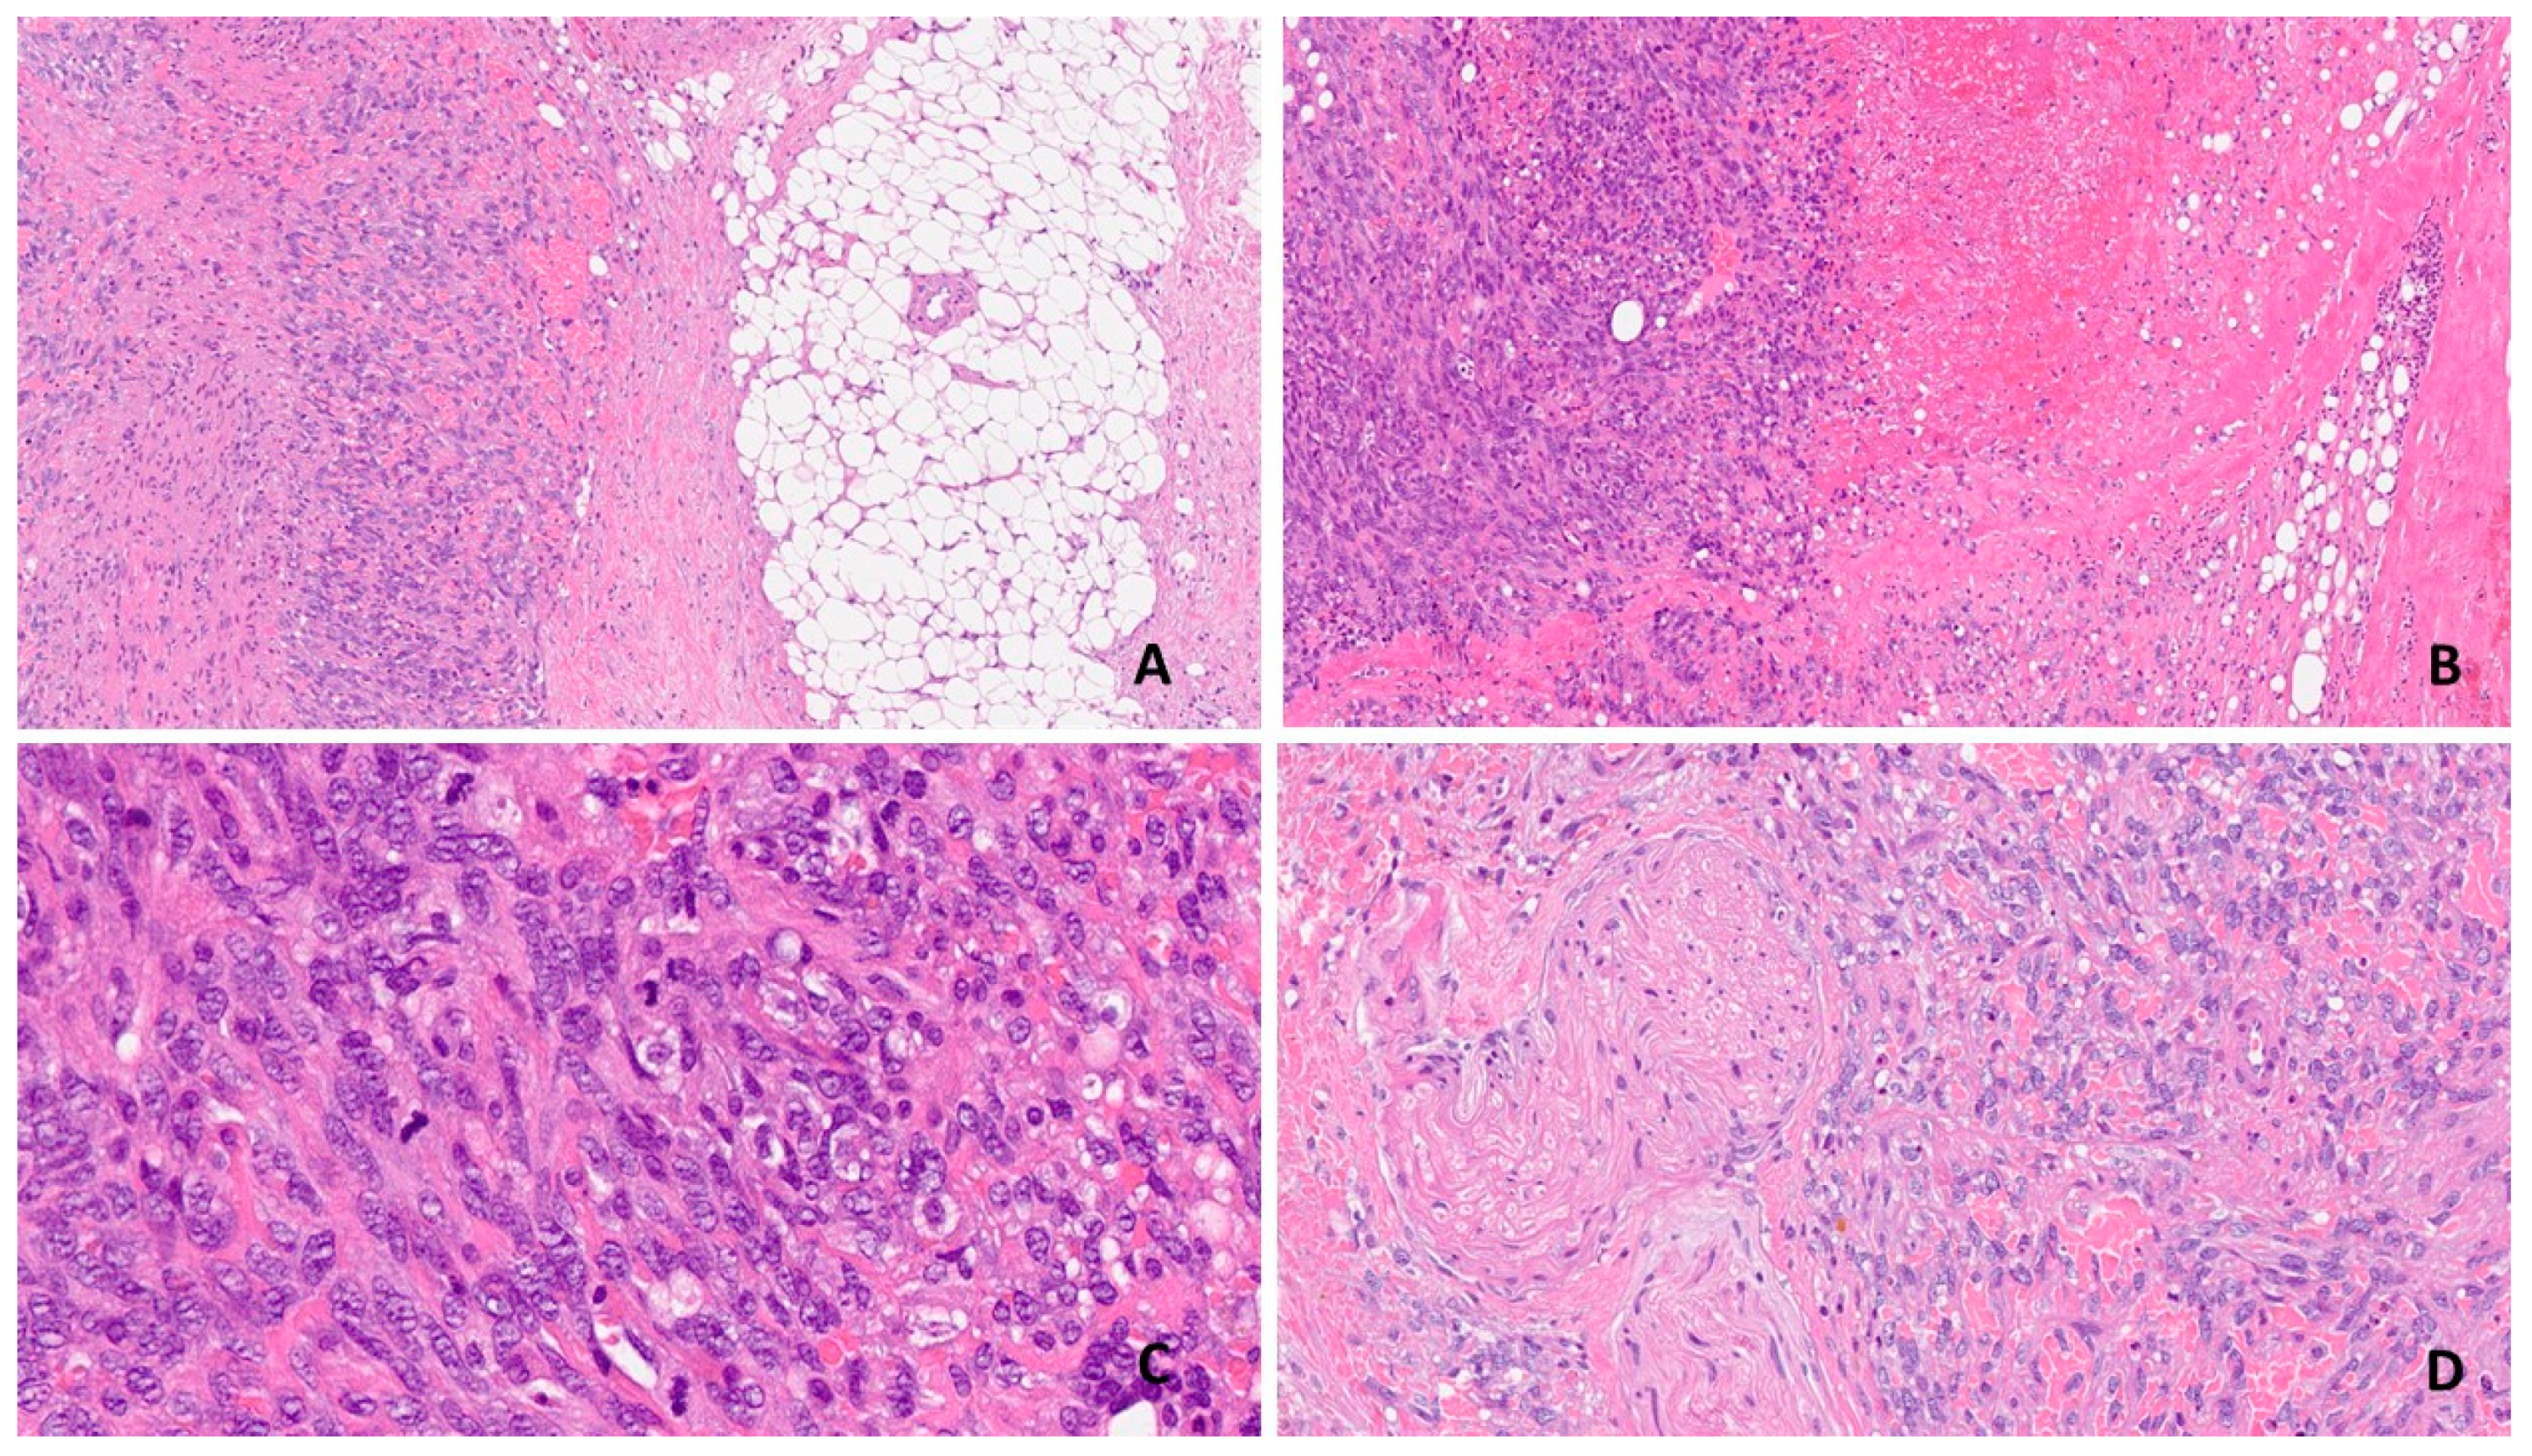

2.1. Pathological Features

2.2. Differential Diagnosis

2.3. Diagnosis